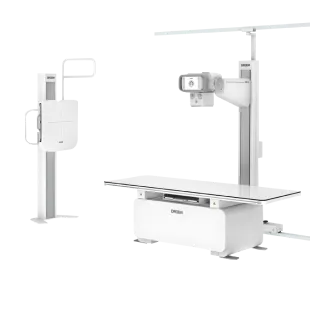

X-ray

X-ray